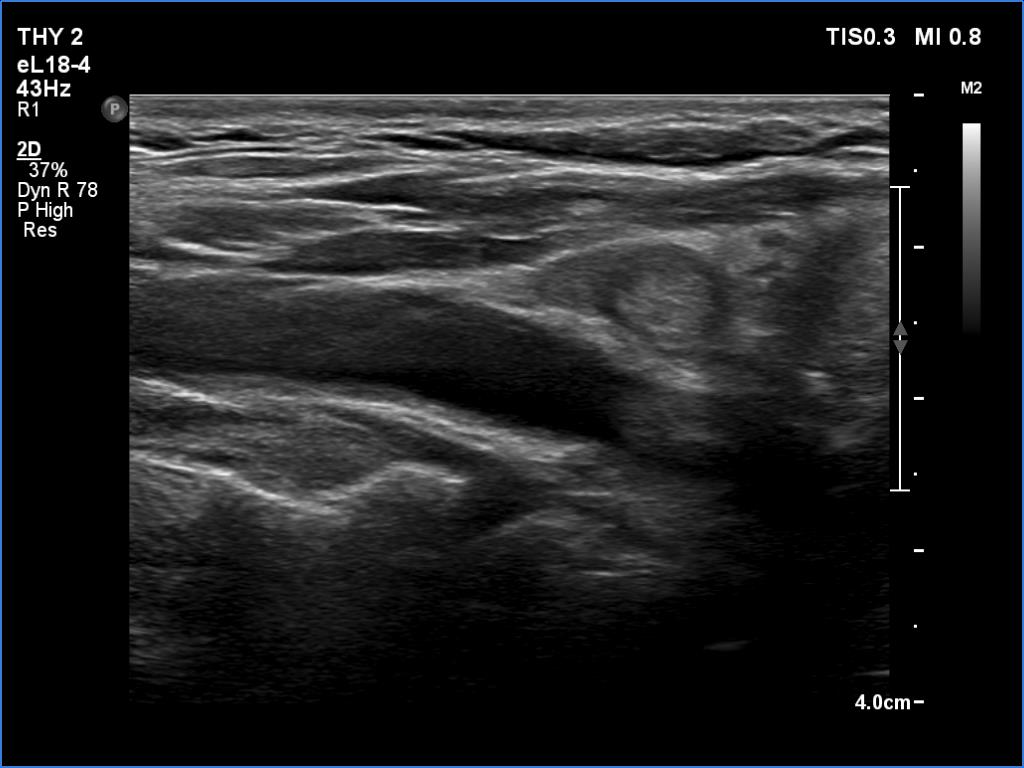

Ultrasonography. Both lobes had discrete lesions. The volume of the lobes were approximately one-tenth and one-third of a normal lobe, right and left lobe, respectively. The possibility of a true nodule should be considered in the event of the lesions in the left lobe.